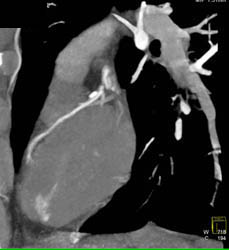

Diseased LAD